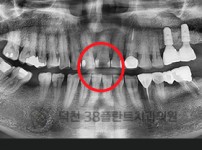

치료전후